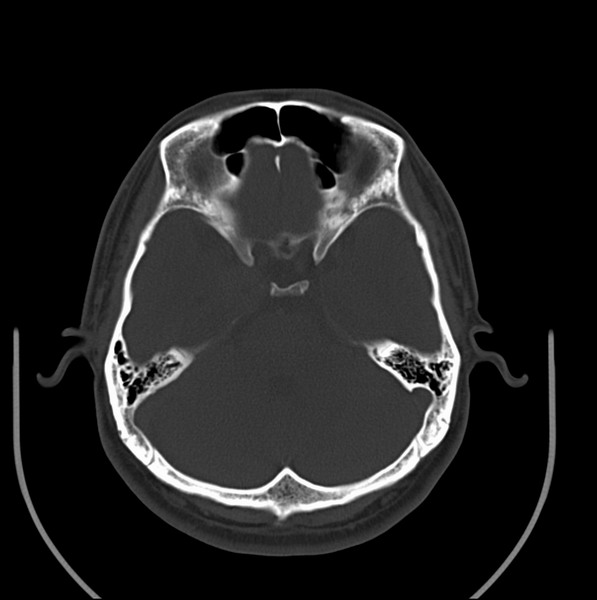

男、30、发现鼻咽部肿瘤侵犯海绵窦,未发现明显淋巴肿。请问国内那家医院治疗鼻咽部肿瘤最好?手术以何种方式为主?病灶可否全部切除?急切期待的大家的帮助。

扫描示鼻咽腔不对称,中度狭窄,右侧咽隐窝消失,局部软组织肿块,鼻咽右侧壁增厚形成肿块,突入鼻咽腔,肿块平扫呈等密度,肿块向深部侵润,右侧翼内外肌受侵,右侧咽旁间隙变窄;向后生长,头长肌界线欠清,向后上生长侵犯同侧颈动脉鞘区。双侧海绵窦增宽,内见软组织影与鼻咽部肿块相连。考虑鼻咽癌。鼻咽癌主要是放射治疗,且效果较好;到当地有治疗设备较大医院治疗即可。

这个病例有点特殊,和常见的鼻咽癌不太一样,以向颅内侵犯为主,骨质破坏区小。鼻咽癌首先要考虑,有没有其他可能?本人不会看mr片,期待有人能讲解,期待病理。

鼻咽部新生物(纤维血管瘤?鼻咽癌?)侵犯右侧中颅窝底及右侧海绵窦;建议必要时活检定性。

鼻咽部新生物侵犯右侧中颅窝底及右侧海绵窦,鼻咽癌可能性大。建议增强扫描。纤维血管瘤禁忌穿刺。

典型鼻咽癌侵犯右侧海绵窦(对放疗敏感)